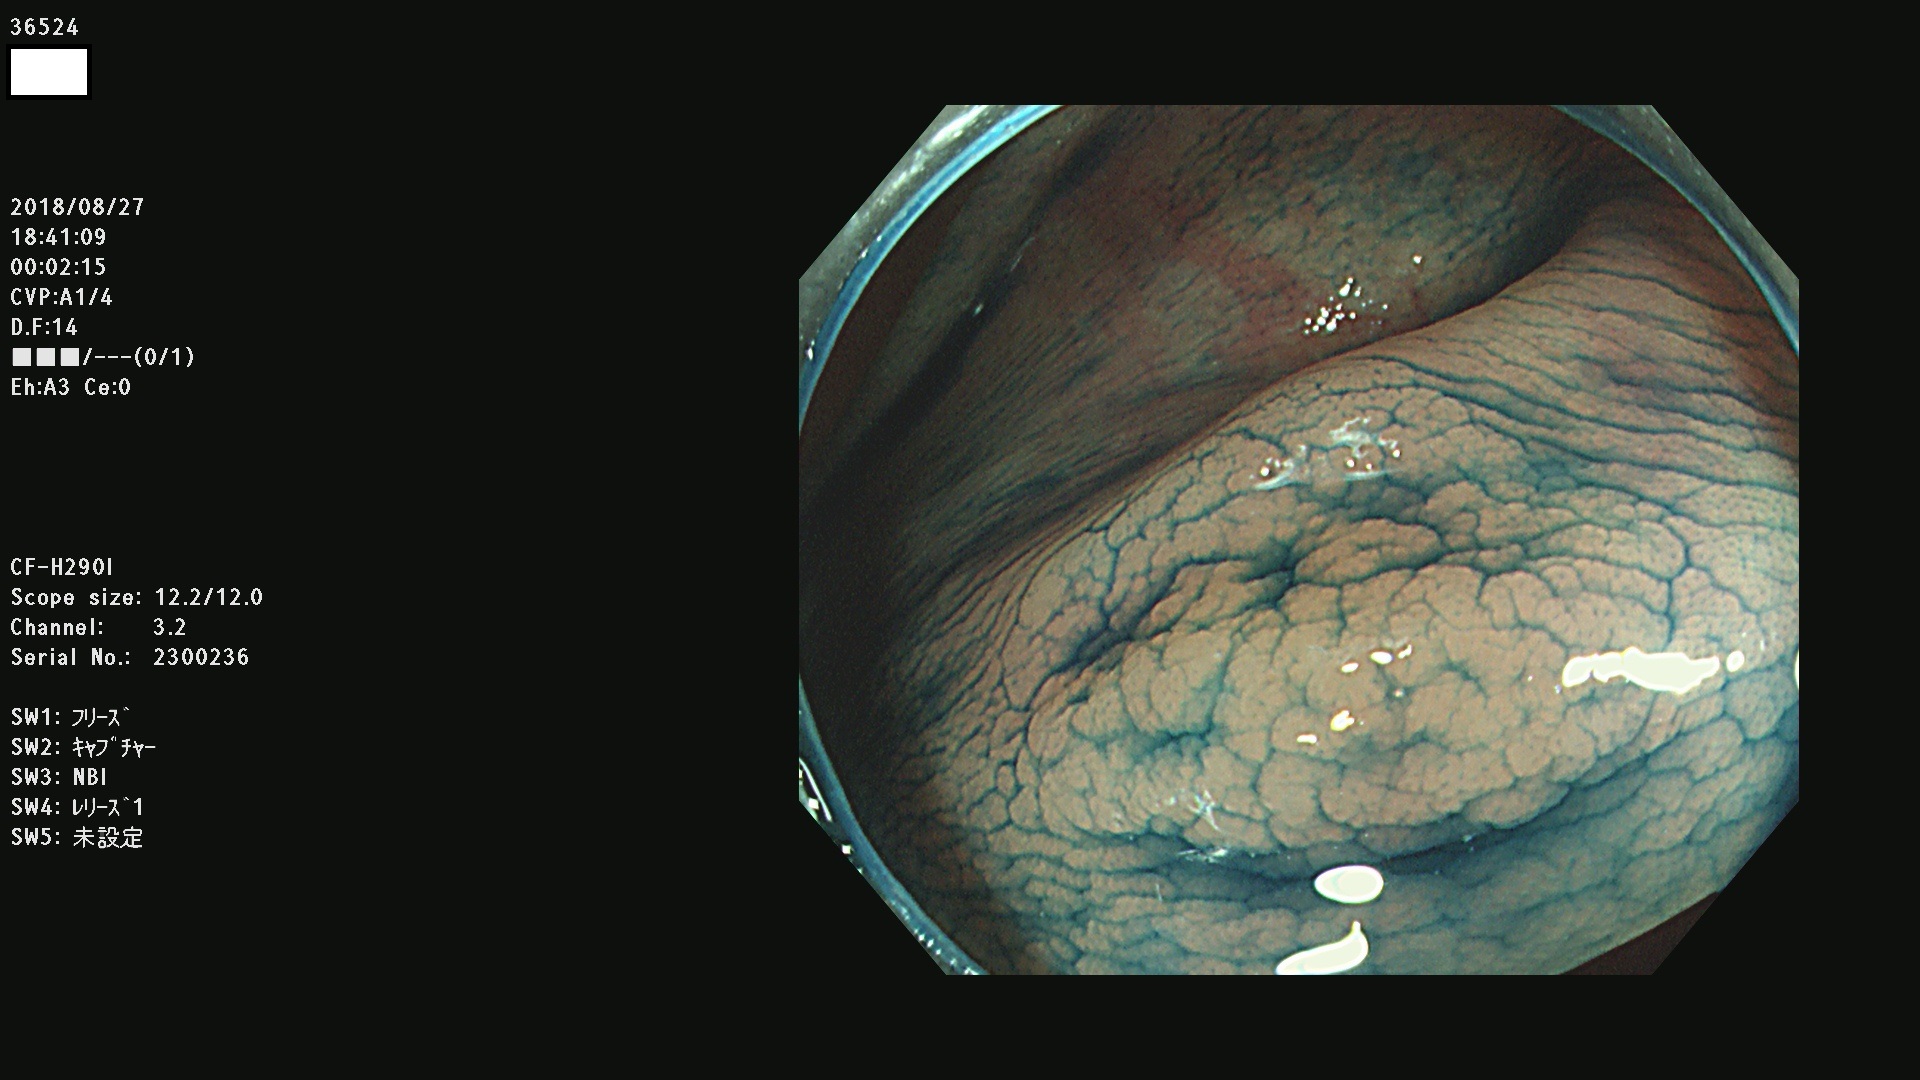

36500 36503 36504 36505 36507(SSAPのみ) 36508 36509 36510 36511 36514 36515 36517 36518 36520 36522(SSAPのみ) 36523 36524 36526 36528 36530 36531 36532 36533 36534 36535 36536 36538 36541 36542 36543 36544 36545 36546 36548 36550 36551 36554 36555 36556 36558 36559 36560 36561 36564 36565 36567 36568 36570 36572 36573 36574 36575 36576 36577 36578 36579 36580 36582 36584 36586 36591 36592 36593 36594 36595 36596 36597 36598

発見困難で危険性の高い平坦型病変(上記100名より抽出)

虫垂SSAP